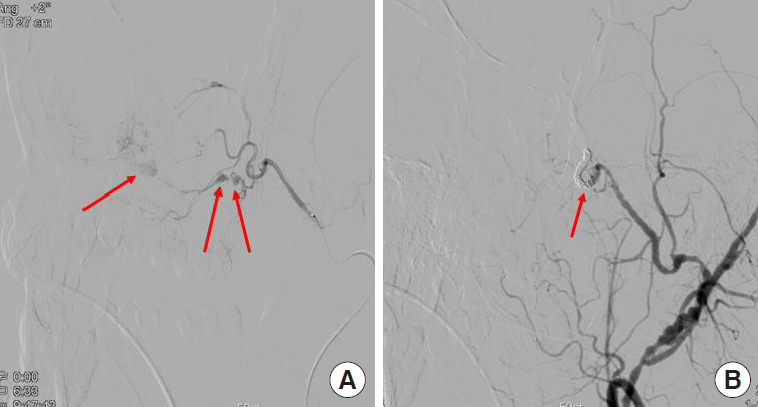

Fig. 3.

Angiographic images. (A) Total of three pseudoaneurysms of the posterior superior alveolar artery (red arrows). A branch of the internal maxillary artery is identified as the bleeding feeder. (B) Through coiling, endovascular embolization of the proximal and distal part of posterior superior alveolar artery was performed, and there was no residual bleeding as soon as the pseudoaneurysms disappeared.